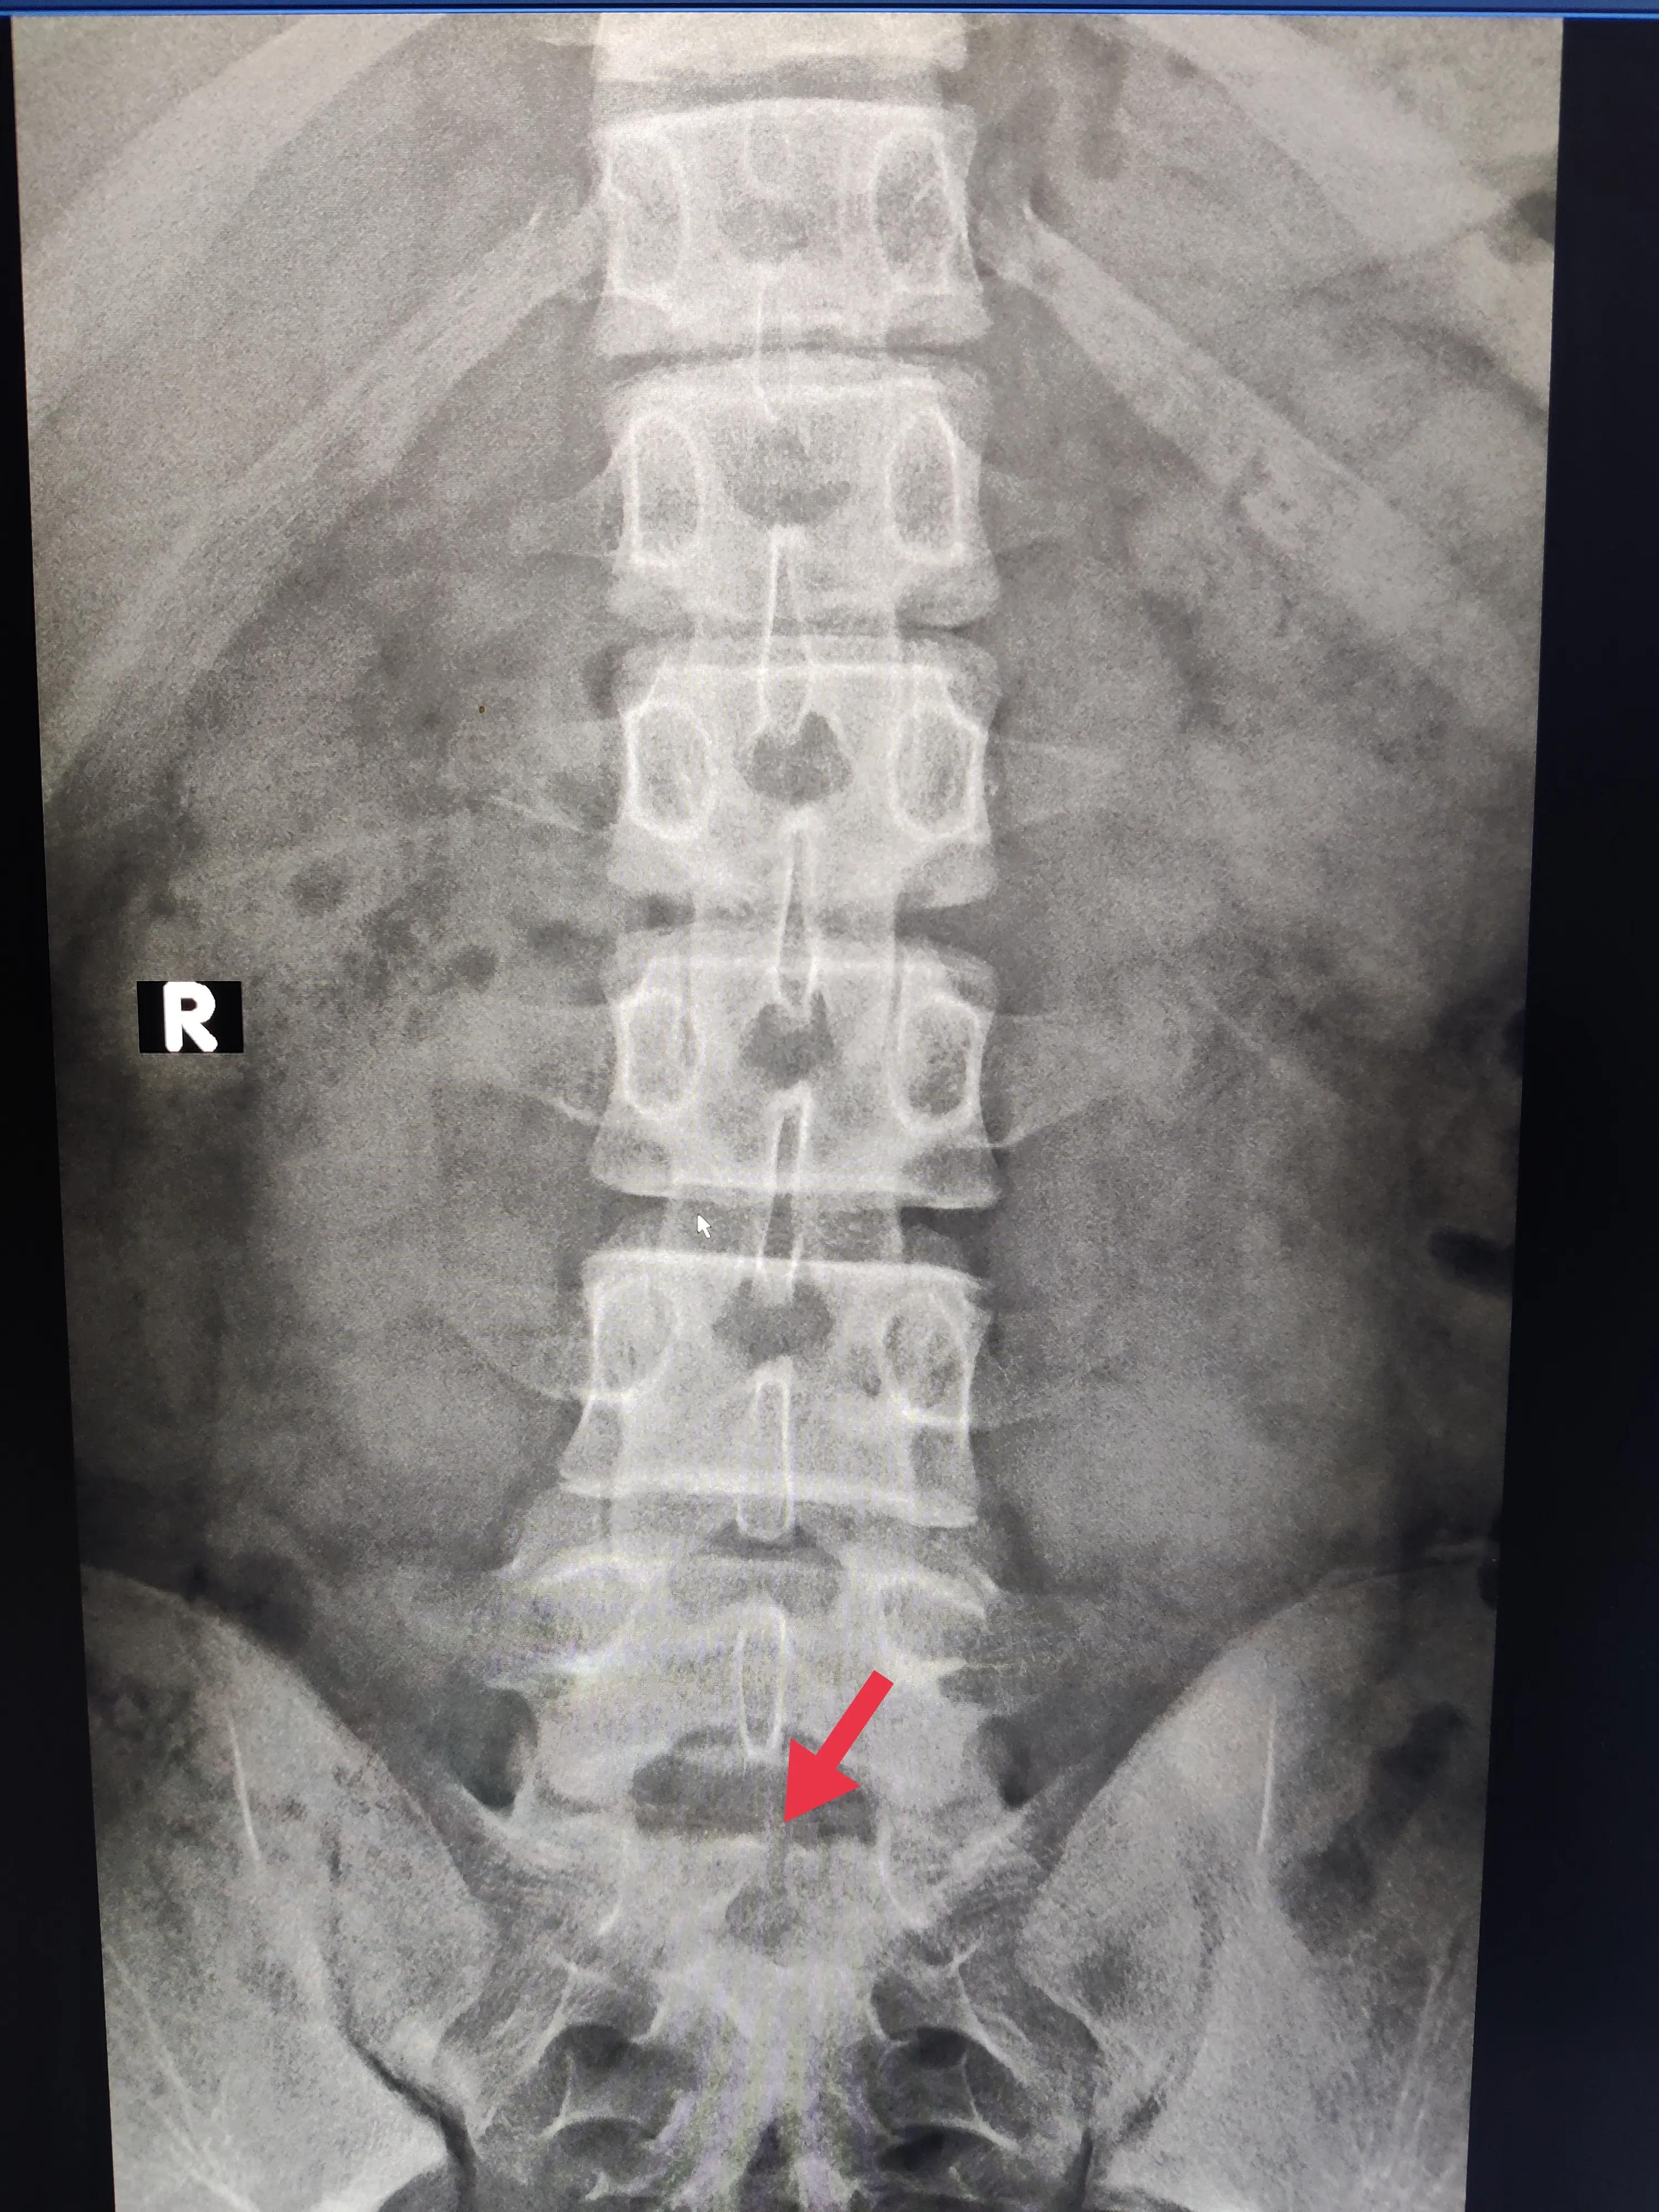

骶1椎体隐形骶裂

胸12、腰1椎体楔形改变,腰1椎体上缘凹凸不平,胸12-腰2椎体上缘不规整。

腰椎楔形改变